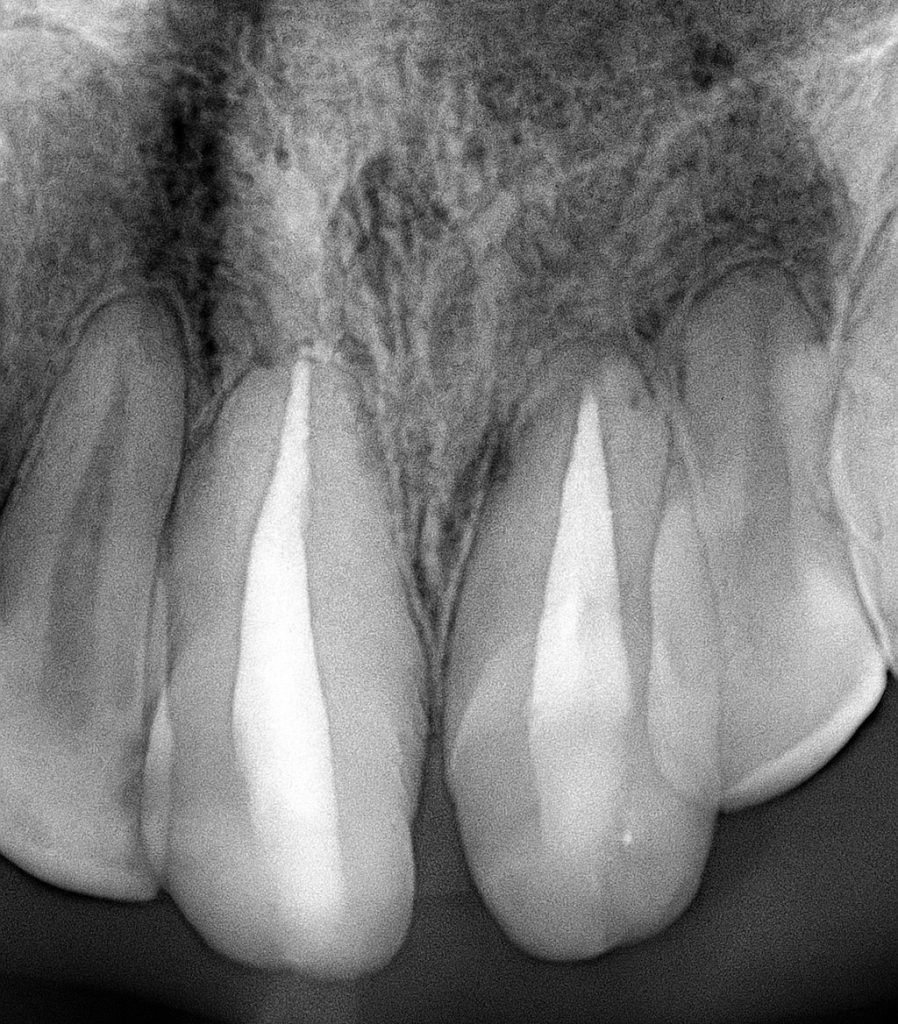

Step 1 — Endodontic Management

Root canal therapy was performed on both centrals due to pulpal exposure and chronic symptoms.

Protocol included:

- Full rubber dam isolation

- Chemomechanical preparation with NaOCl + EDTA

- Shaping with controlled torque instrumentation

- Warm vertical obturation for dense apical seal

- Post-endo coronal build-up for crown retention

This provided a stable biological foundation before prosthetic steps.